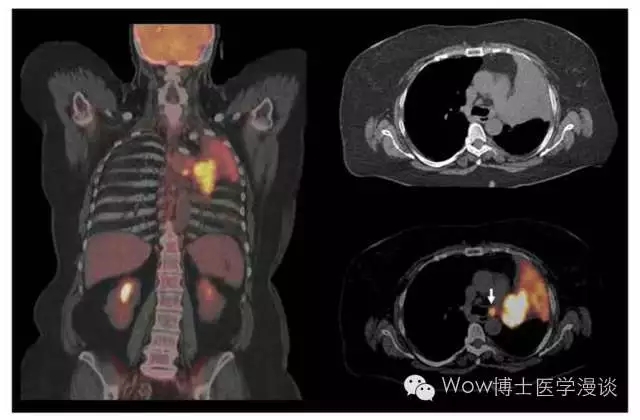

PET/CT可以提供病灶的代谢和精确位置等信息

比如上面这个示意图,如果右侧的肺脏长了肿瘤。我们通过PET/CT就可以清晰得看到这一侧的肺脏里边有“高代谢区域”——也就是摄取了大量核素标记的葡萄糖的区域,可以帮助我们精确定位肿瘤的位置,同时观察是否存在转移以及转移的位置。

PET/CT的分辨率和定位能力优于单纯的PET技术